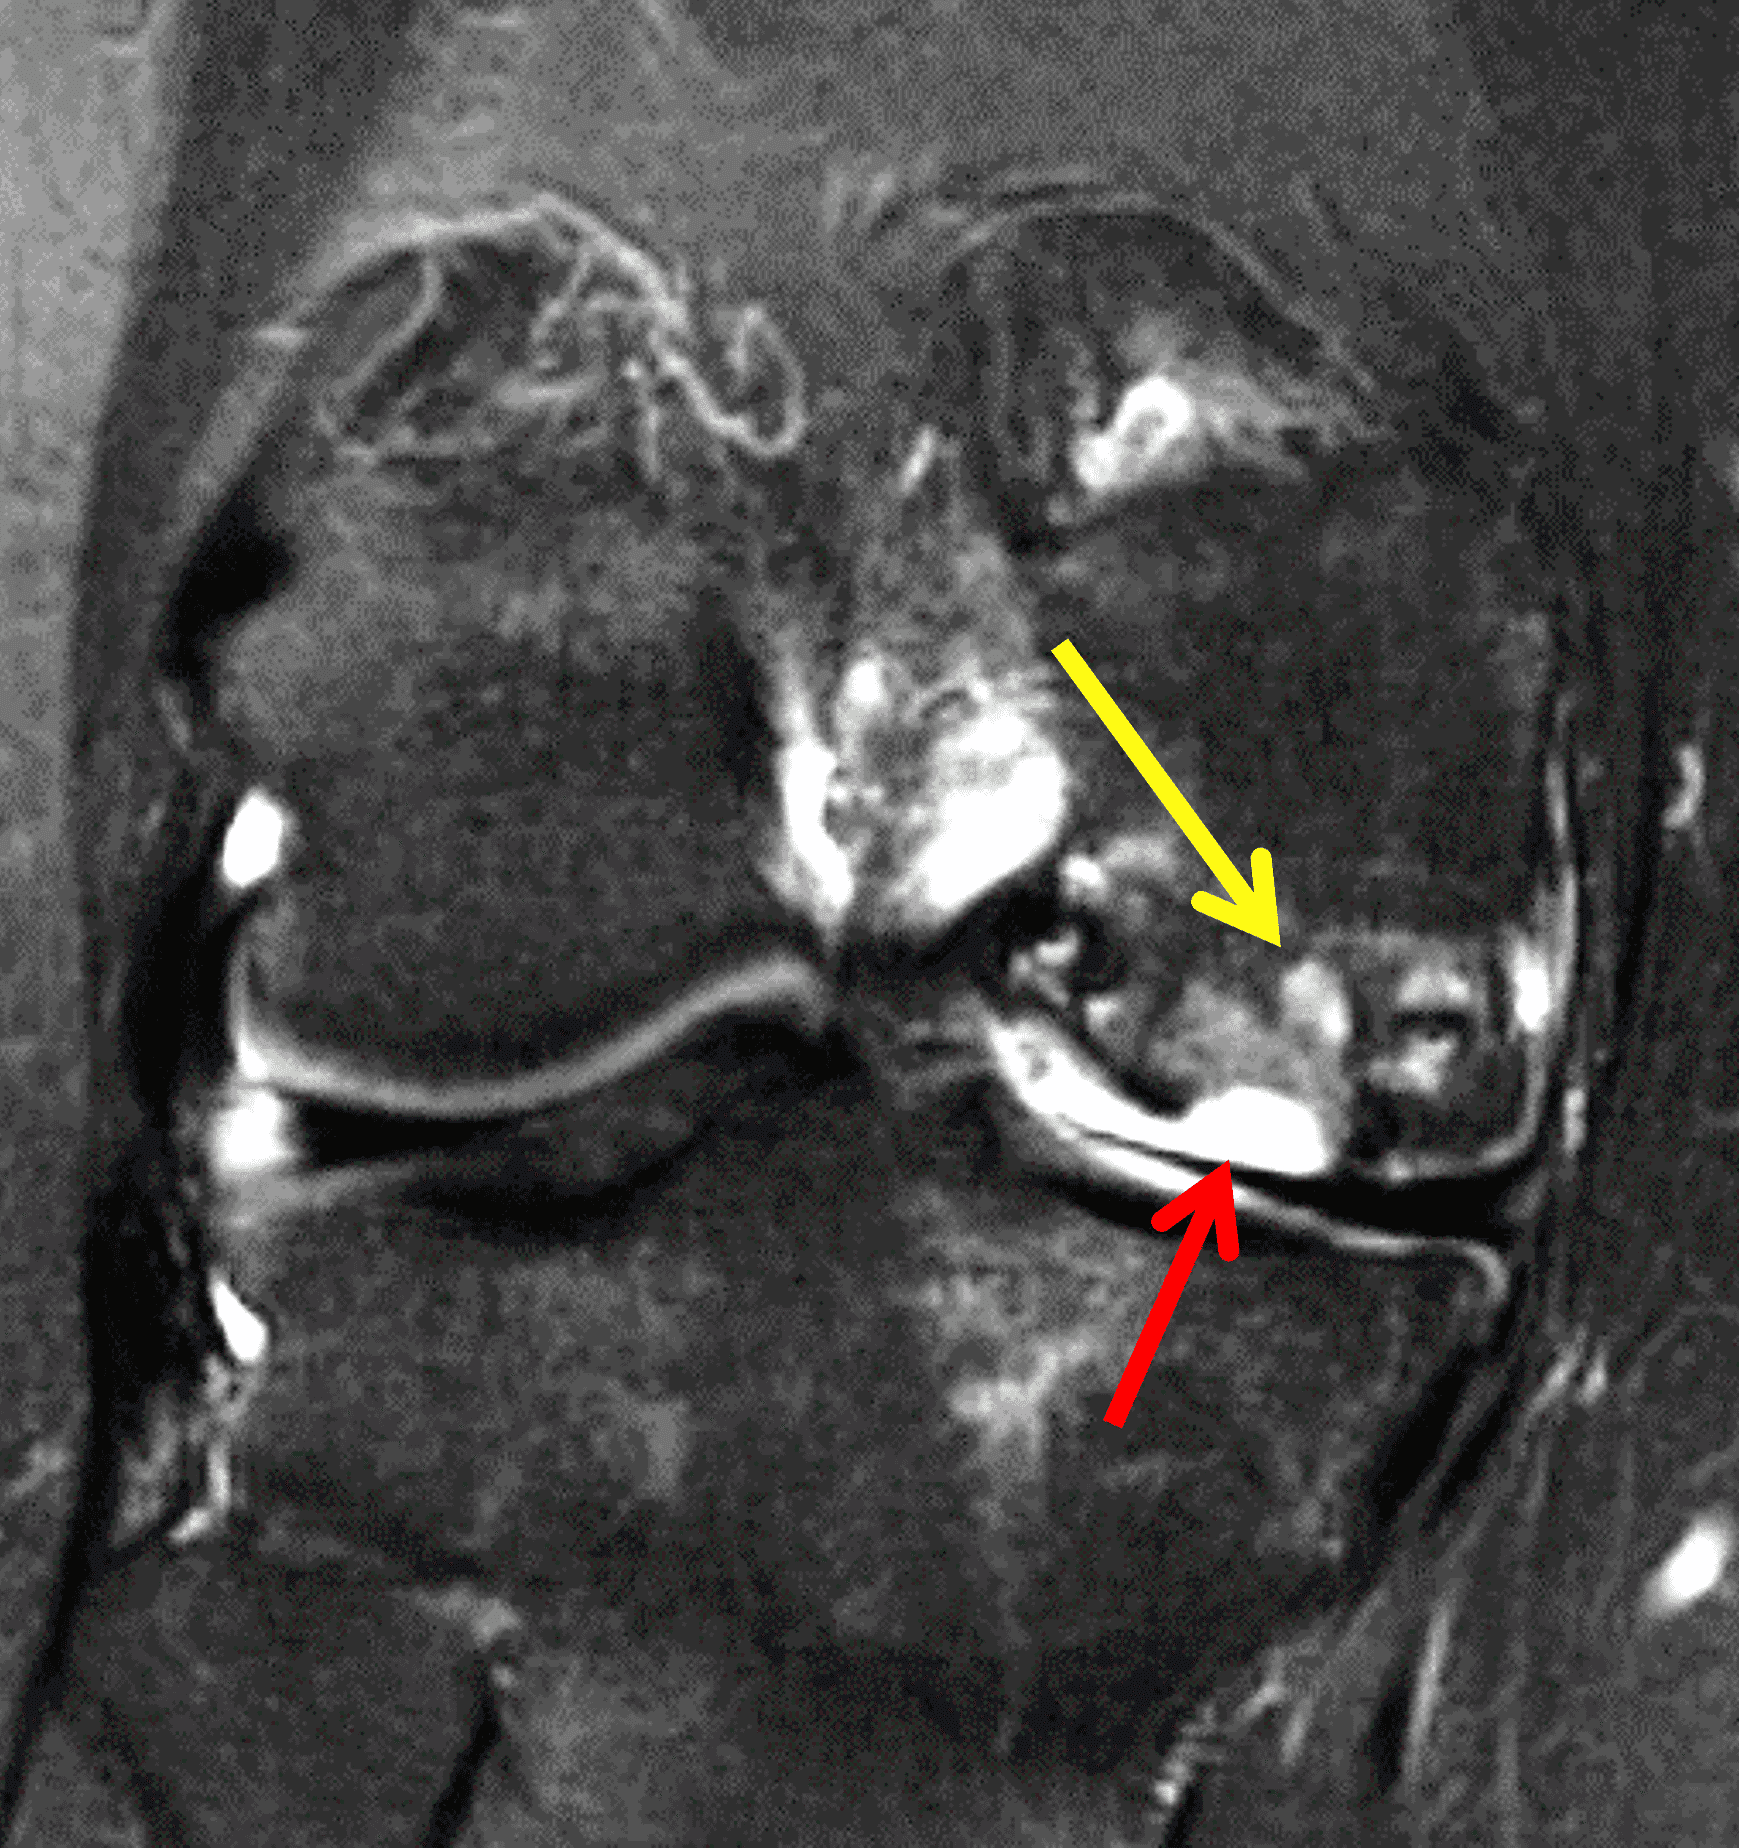

A 32-year-old man suffered a traumatic chondral injury to the medial femoral condyle that was treated with an osteochondral allograft 20 months previously. Representative images from a current knee MRI include (1A) coronal fat-suppressed fluid-sensitive and sagittal (1B) T1-weighted, (1C) proton density-weighted, and (1D) T2-weighted sequences. Are the post-operative MRI findings normal and expected, or abnormal and pathologic? Based on these images, would you characterize the procedure as a success or failure?

Figure 2: (2A) On the coronal image, the margins of the osteochondral graft are faintly visible (arrowheads). Both the graft and underlying bone show mild marrow edema, an expected finding. (2B) The T1-weighted image shows continuity of the marrow in the graft (asterisks) with the underlying bone, indicating osseous integration. A bioabsorbable pin (arrow) used for graft fixation is partly visible. (2C) The proton density-weighted image shows a low signal intensity seam (black arrow) between the native cartilage and transplant, as well as a defect in the subchondral bone plate of the graft (red arrow) where the pin was drilled, both normal findings. (2D) The T2-weighted image shows a smooth, congruent articular surface (arrows), restoring the normal anatomy, and a tiny subchondral cyst. No findings are present to suggest graft failure. The patient’s current symptoms were attributed to pathology elsewhere in the joint (not shown).

The postoperative imaging appearance of osteochondral allografts is similar to autografts (Figure 2).33 The subchondral bone plate of the donor and recipient sites do not have to match, but the articular surface should be congruent. Grafts that fail to incorporate by one year have a poor prognosis. Persistent marrow edema (beyond 12 months), a thick graft interface containing cysts or fluid, and subsidence of the graft are associated with poor osseous healing and worse outcomes. Extensive host marrow edema and severe synovitis may be a clue to immunologic rejection of the graft (Figure 18).21, 34